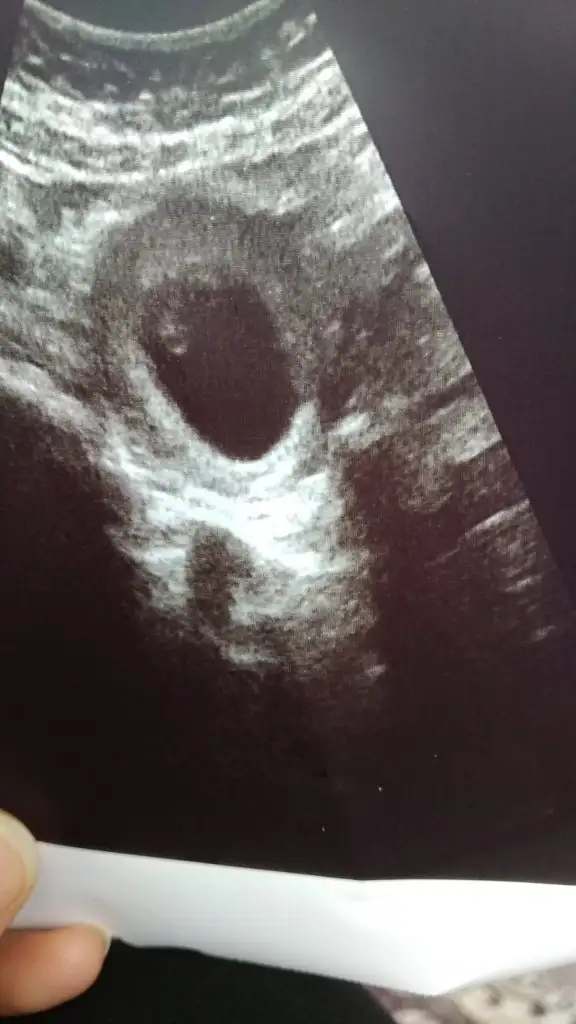

Bugün 7+1 kalp atışını duyduk şükür ama çok küçücük daha 6 haftalık görüldü haftaya yine çağırdı

• IMG-20210317-WA0116.webp

IMG-20210317-WA0116.webp

25,3 KB · Görüntüleme: 43

Bende anlamadım neden çağırdığını tahlil değil ama bütün tahlillerim geçen hafta yapıldı.heralde çok küçük görüldü diye düşündüm